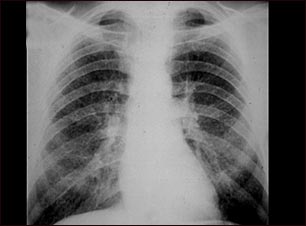

Neumoconiosis del minero en etapa II

Esta radiografía de tórax muestra la neumoconiosis del minero etapa II (CWP, por sus siglas en inglés). A ambos lados del pulmón hay áreas difusas, pequeñas y claras. Otras enfermedades que pueden explicar estos hallazgos en una radiografía son, entre otras: la silicosis simple, la tuberculosis diseminada, cáncer metastásico de pulmón y otras enfermedades pulmonares infiltrativas y difusas.